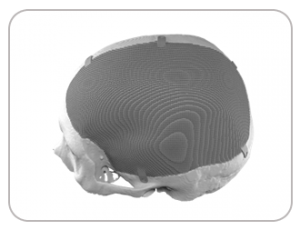

DEFECT FROM HEAD INJURY

IMPLANT FABRICATED USING 3D PRINTING TECHNOLOGY

POST-SURGERY SCAN IMAGE AFTER 24 MONTHS SHOWING PERFECT IMPLANT FIT